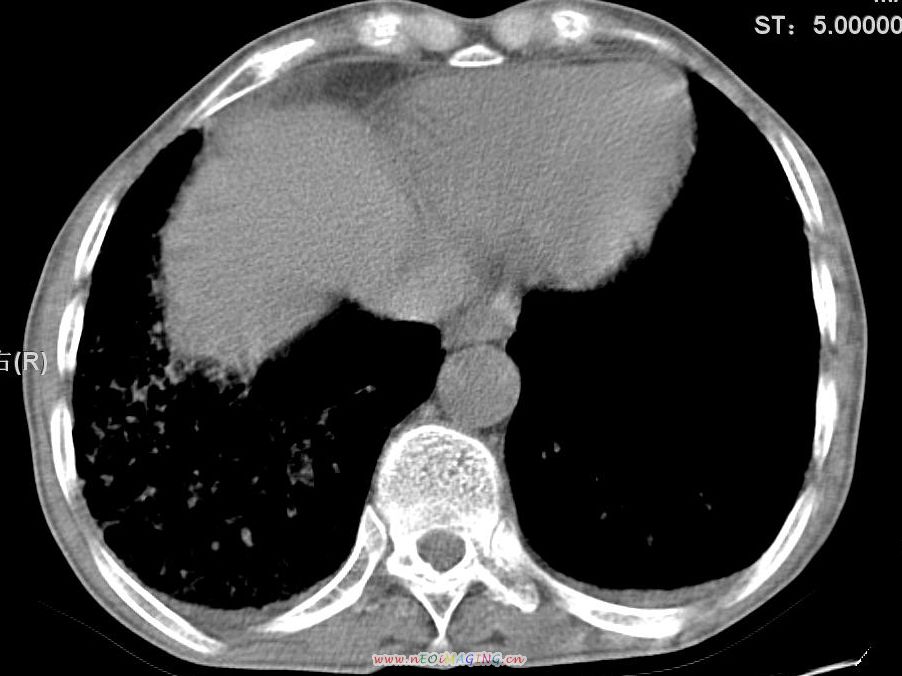

患者咳嗽月余,高热数天,咳黄色稍脓痰。

双肺野分布多个小结节状高密度影,其内散在斑片状模糊影,气管。支气管通畅,纵隔内淋巴结钙化,胸膜局限性增厚粘连,胸腔少量积液。结合病史考虑结核并感染的可能性大,胸膜炎并积液。肺泡癌待排。

纵隔内见钙化的淋巴节,上肺见钙化灶,双肺均匀弥漫分布小结节影,边缘较清楚,能不能考虑是在矽肺的基础上并发的结核和感染,请详细了解病史结合临床.

高热数天,咳黄色稍脓痰,肯定应该有急性化脓性感染,左上叶舌段及右肿叶可见多量斑片状及支气管气像,首先考虑肺部感染合并血型播散性肺脓肿(脓肿为早期改变),其次不排除有肺泡癌,第三不排除结核,建议治疗后复查